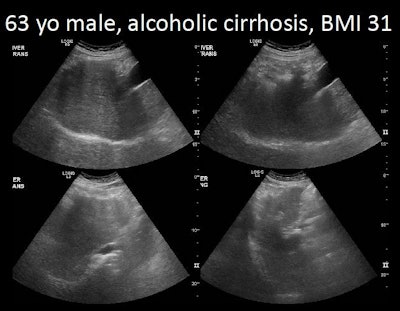

In a small, retrospective review, the UCSD team found that nearly two-thirds of ultrasound studies performed for HCC surveillance were considered inadequate in quality, as determined by visualization and penetration of the liver. Key factors affecting exam quality included high body mass index (BMI), ascites, and the presence of cirrhosis, according to Dr. Yuko Kono, PhD, an associate clinical professor of medicine in the division of gastroenterology and hepatology and an associate clinical professor of radiology.

A high BMI (p ≤ 0.001), ascites (p = 0.039), and cirrhosis (p = 0.042) were considered the main limiting factors in the quality of the inadequate studies, according to multivariate analysis. Liver international normalized ratio (INR) was not a statistically significant factor (p = 0.089).